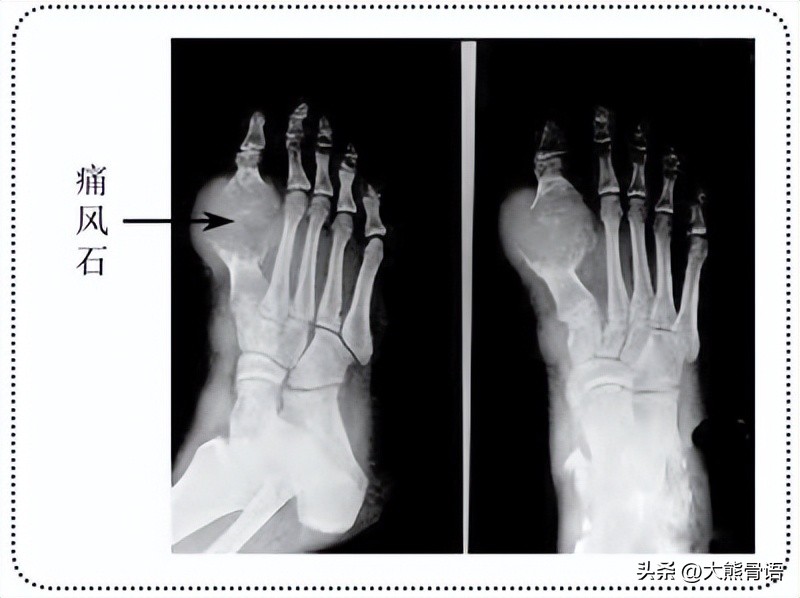

或许你会觉得没关系,也就是痛那么几天,男子汉大丈夫,忍一忍或者随便吃点药就好了。图样图森破!长久下去这些尿酸盐结晶会形成 “痛风石”,而关节内大量沉积的痛风石可能会造成关节骨质破坏、纤维化等!不管是单纯的高尿酸血症,还是痛风性关节炎,都有可能导致如:痛风性肾病、尿酸性肾结石等肾脏并发症,对肾功能造成损害,严重的会导致肾衰!

被痛风石损害的第一跖趾关节